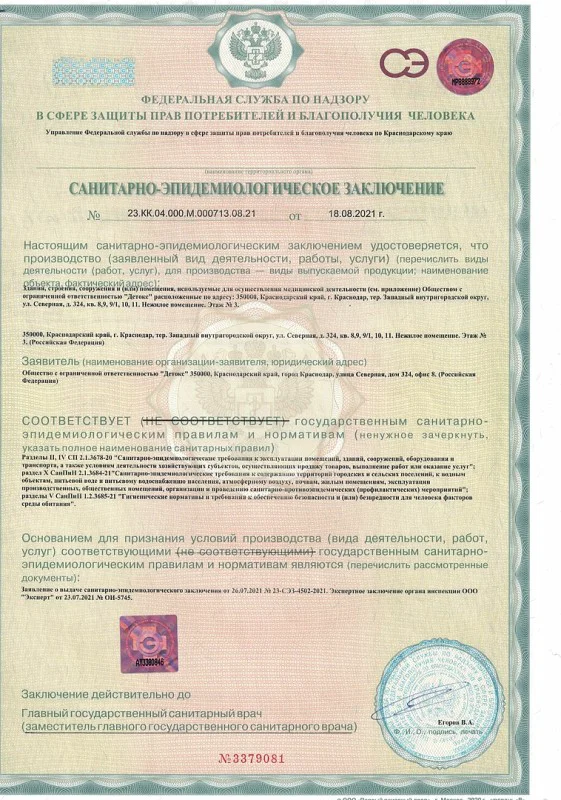

Лицензия на осуществление медицинской деятельности

Лицензия на осуществление медицинской деятельности

Лицензия на осуществление медицинской деятельности

Лицензия на осуществление медицинской деятельности

Лицензия на осуществление медицинской деятельности

Лицензия на осуществление медицинской деятельности

Лицензия на осуществление медицинской деятельности

Лицензия на осуществление медицинской деятельности